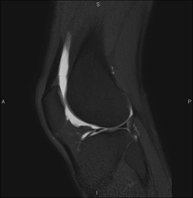

Exploració ideal per estudiar les lesions en músculs isquiotibials i quàdriceps, sovint lesionats en esportistes. També permet una bona valoració de tendons i de nervis perifèrics. La durada aproximada és de 20 minuts. No utilitza radiació ionitzan. - RM de Genoll

Exploració per estudiar lesions a l'articulació, com trencaments dels meniscals i dels lligaments creuats (únicament es poden detectar amb aquesta prova), condropatia o desgast del cartílag i moltes altres alteracions derivades de l'activitat esportiva i dels canvis degeneratius (osteoartrosi). La durada aproximada és de 18 minuts. No utilitza radiació ionitzant. - RM de Cama